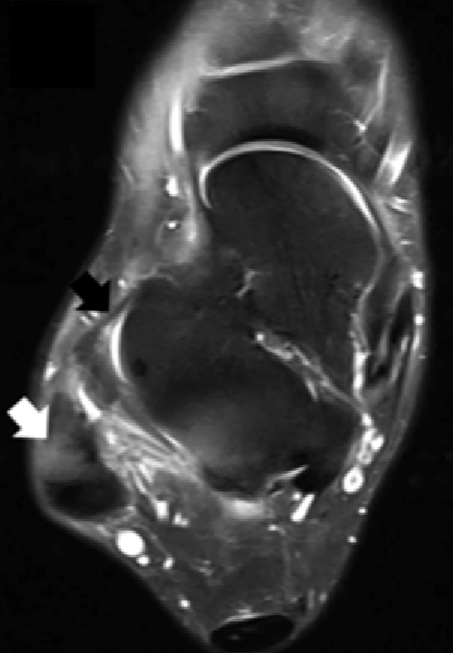

其三,副骨有肌腱或韧带附着,当发生扭伤或者反复的运动时,副骨与正常骨之间的纤维软骨可能发生联合撕裂,引起副骨不稳定,进而出现关节不稳。例如腓骨下游离小骨,部分会附着踝关节外侧韧带,踝扭伤后会出现踝关节不稳症状。

而对于纤维软骨联合撕裂引发的副骨和关节不稳定,需要尽早规范治疗。在外伤后可以立即用石膏或支具固定一段时间,以帮助撕裂的纤维软骨联合愈合。若拆除固定后仍有关节不稳定或疼痛,则建议手术治疗。